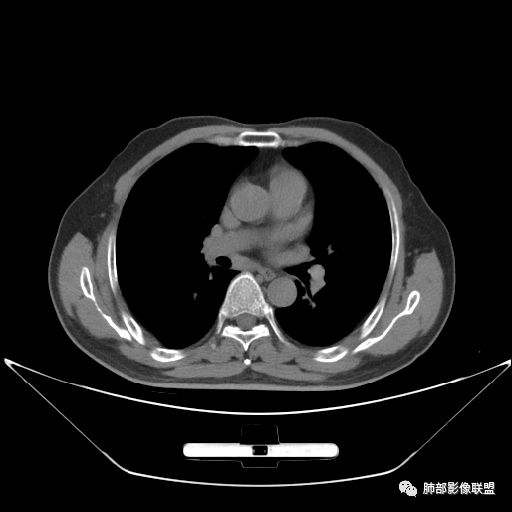

住院4天后行胸部增强CT

静脉期

老年男性,因“咳嗽咳痰1月余。”入院。病程中咳嗽咳痰,咳黄白痰,间断咯少许鲜红色痰血。PPD阳性。胸CT:右肺中叶外侧段支气管管腔阻塞,大片实性病变,病灶边缘光滑,部分边缘膨隆,可见分叶,肺门及纵隔可见肿大淋巴结,并可见钙化。增强可见病灶明显强化,而且延迟强化明显,病灶内多发低密度区,内见血管影,血管变细、部分血管破坏。考虑恶性病变可能性大,鉴别慢性肉芽肿性病变。

胸CT:跨叶大肿块,主体在中叶,右中叶外侧段支气管阻塞,病灶部分边缘膨隆,可见分叶,部分边缘平直,肺门及纵隔可见肿大淋巴结。增强病灶不均匀强化,延迟强化明显,病灶内多发低密度区,内见血管飘浮,部分血管变细、模糊。考虑:恶性病变可能性大,大细胞?淋巴瘤?鉴别慢性肉芽肿性病变。

吴婧老师和南边老师都对该病例进行了深入分析。从支气管管壁的增厚,支气管狭窄后扩张,支气管粘液栓,病灶形态,到病灶不均匀强化及坏死彻底,到周边病灶及肺组织空气的潴留,加之纵隔内淋巴结肿大伴钙化等等,都支持慢性炎性病灶,尤其是结核。